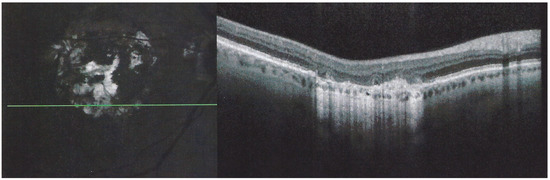

Figure 20. APMPPE/AMIC at first presentation elsewhere. FA early frame (left) shows two areas of non-perfusion, which are better delineated by the ICGA intermediate phase (middle frame) and late phase (right frame).

A 55-year-old man presented a febrile “viral” episode 3 weeks after travelling to Indochina followed by a decrease of vision in his left eye with photopsia. The diagnosis of APMPPE was made elsewhere and it was decided not to introduce systemic treatment “as the disease is self-limited”. FA/ICGA performed was compatible with APMPPE/AMIC (Figure 20).